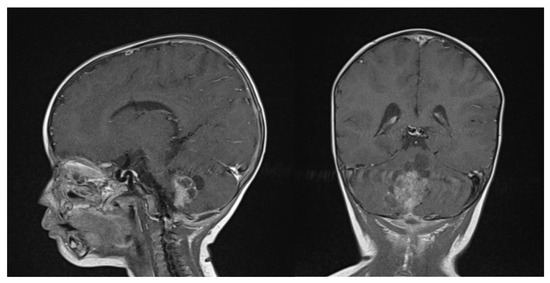

Clinical examination did not show any anterior fontanel bulging nor trismus. Whole brain and spine magnetic resonance imaging (MRI) was performed, showing a heterogeneous cystic-hemorrhagic lesion, partially calcified, in the posterior fossa, Measuring 46 × 34 × 49 mm and obstructing the IV ventricle and right Luschka foramen (Figure 2).

Figure 2.

Sagittal and axial gadolinium T1 MR sequence showing the exophytic mass occluding CSF diversion at the IV ventricle, compressing the brainstem and adjacent right cerebellar hemisphere.